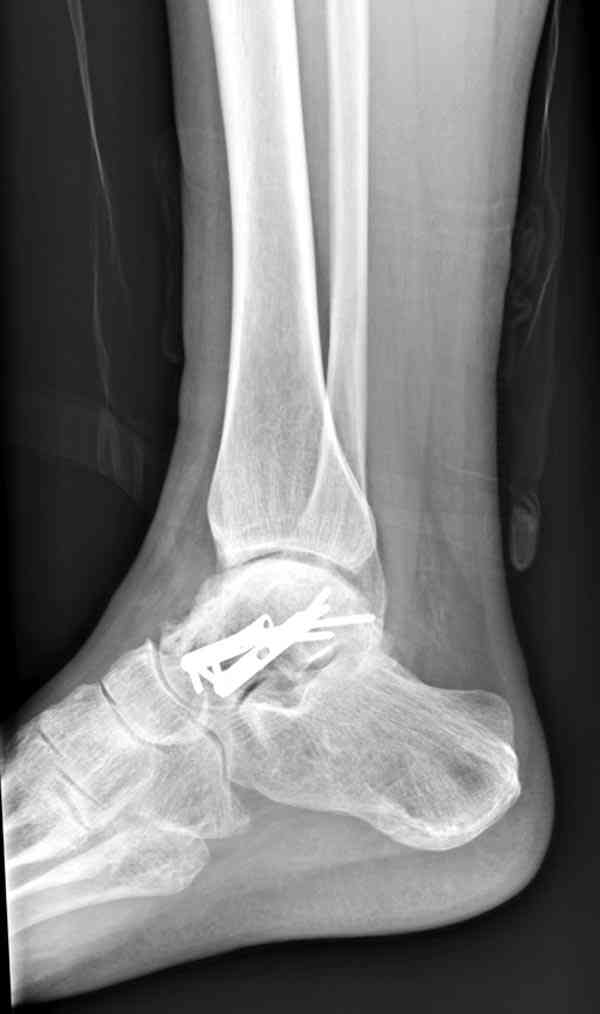

Случай с множественным оскольчатым переломом тарана оперированный из двойного доступа.

Через 2 мес.:

Через 8 мес.:

Через 14 мес.: